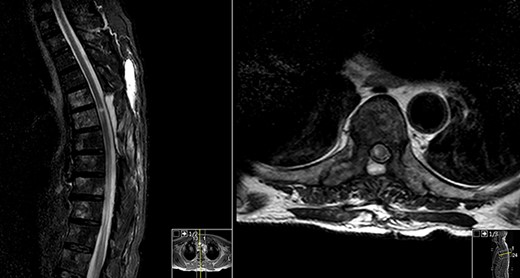

Spinal magnetic resonance imaging (MRI) (Fig. 1) showed an hyperintense contrast-enhancing abnormal mass at the level of T6 which occupied the left side of the spinal canal and compressed the spinal cord.